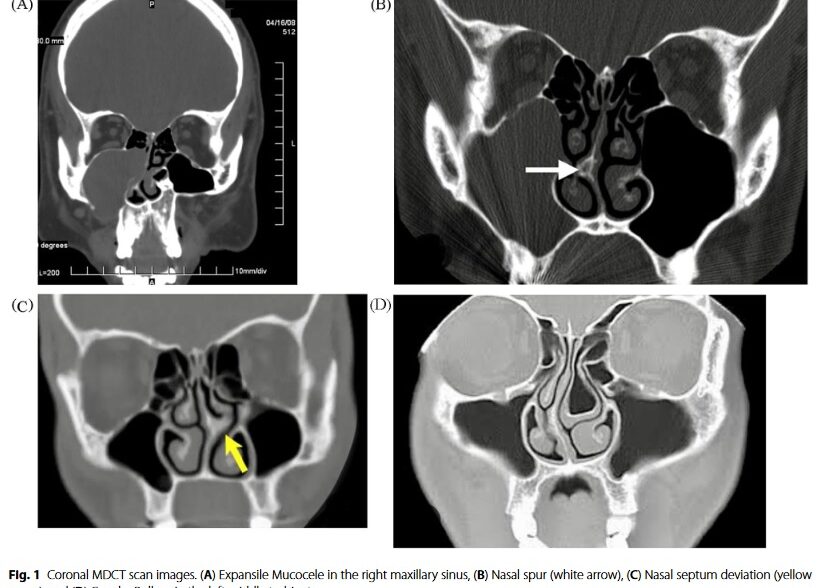

Evaluation of diagnostic accuracy of cone beam computed tomography and multi- detector computed tomography for detection of anatomical variations in rhinoplasty